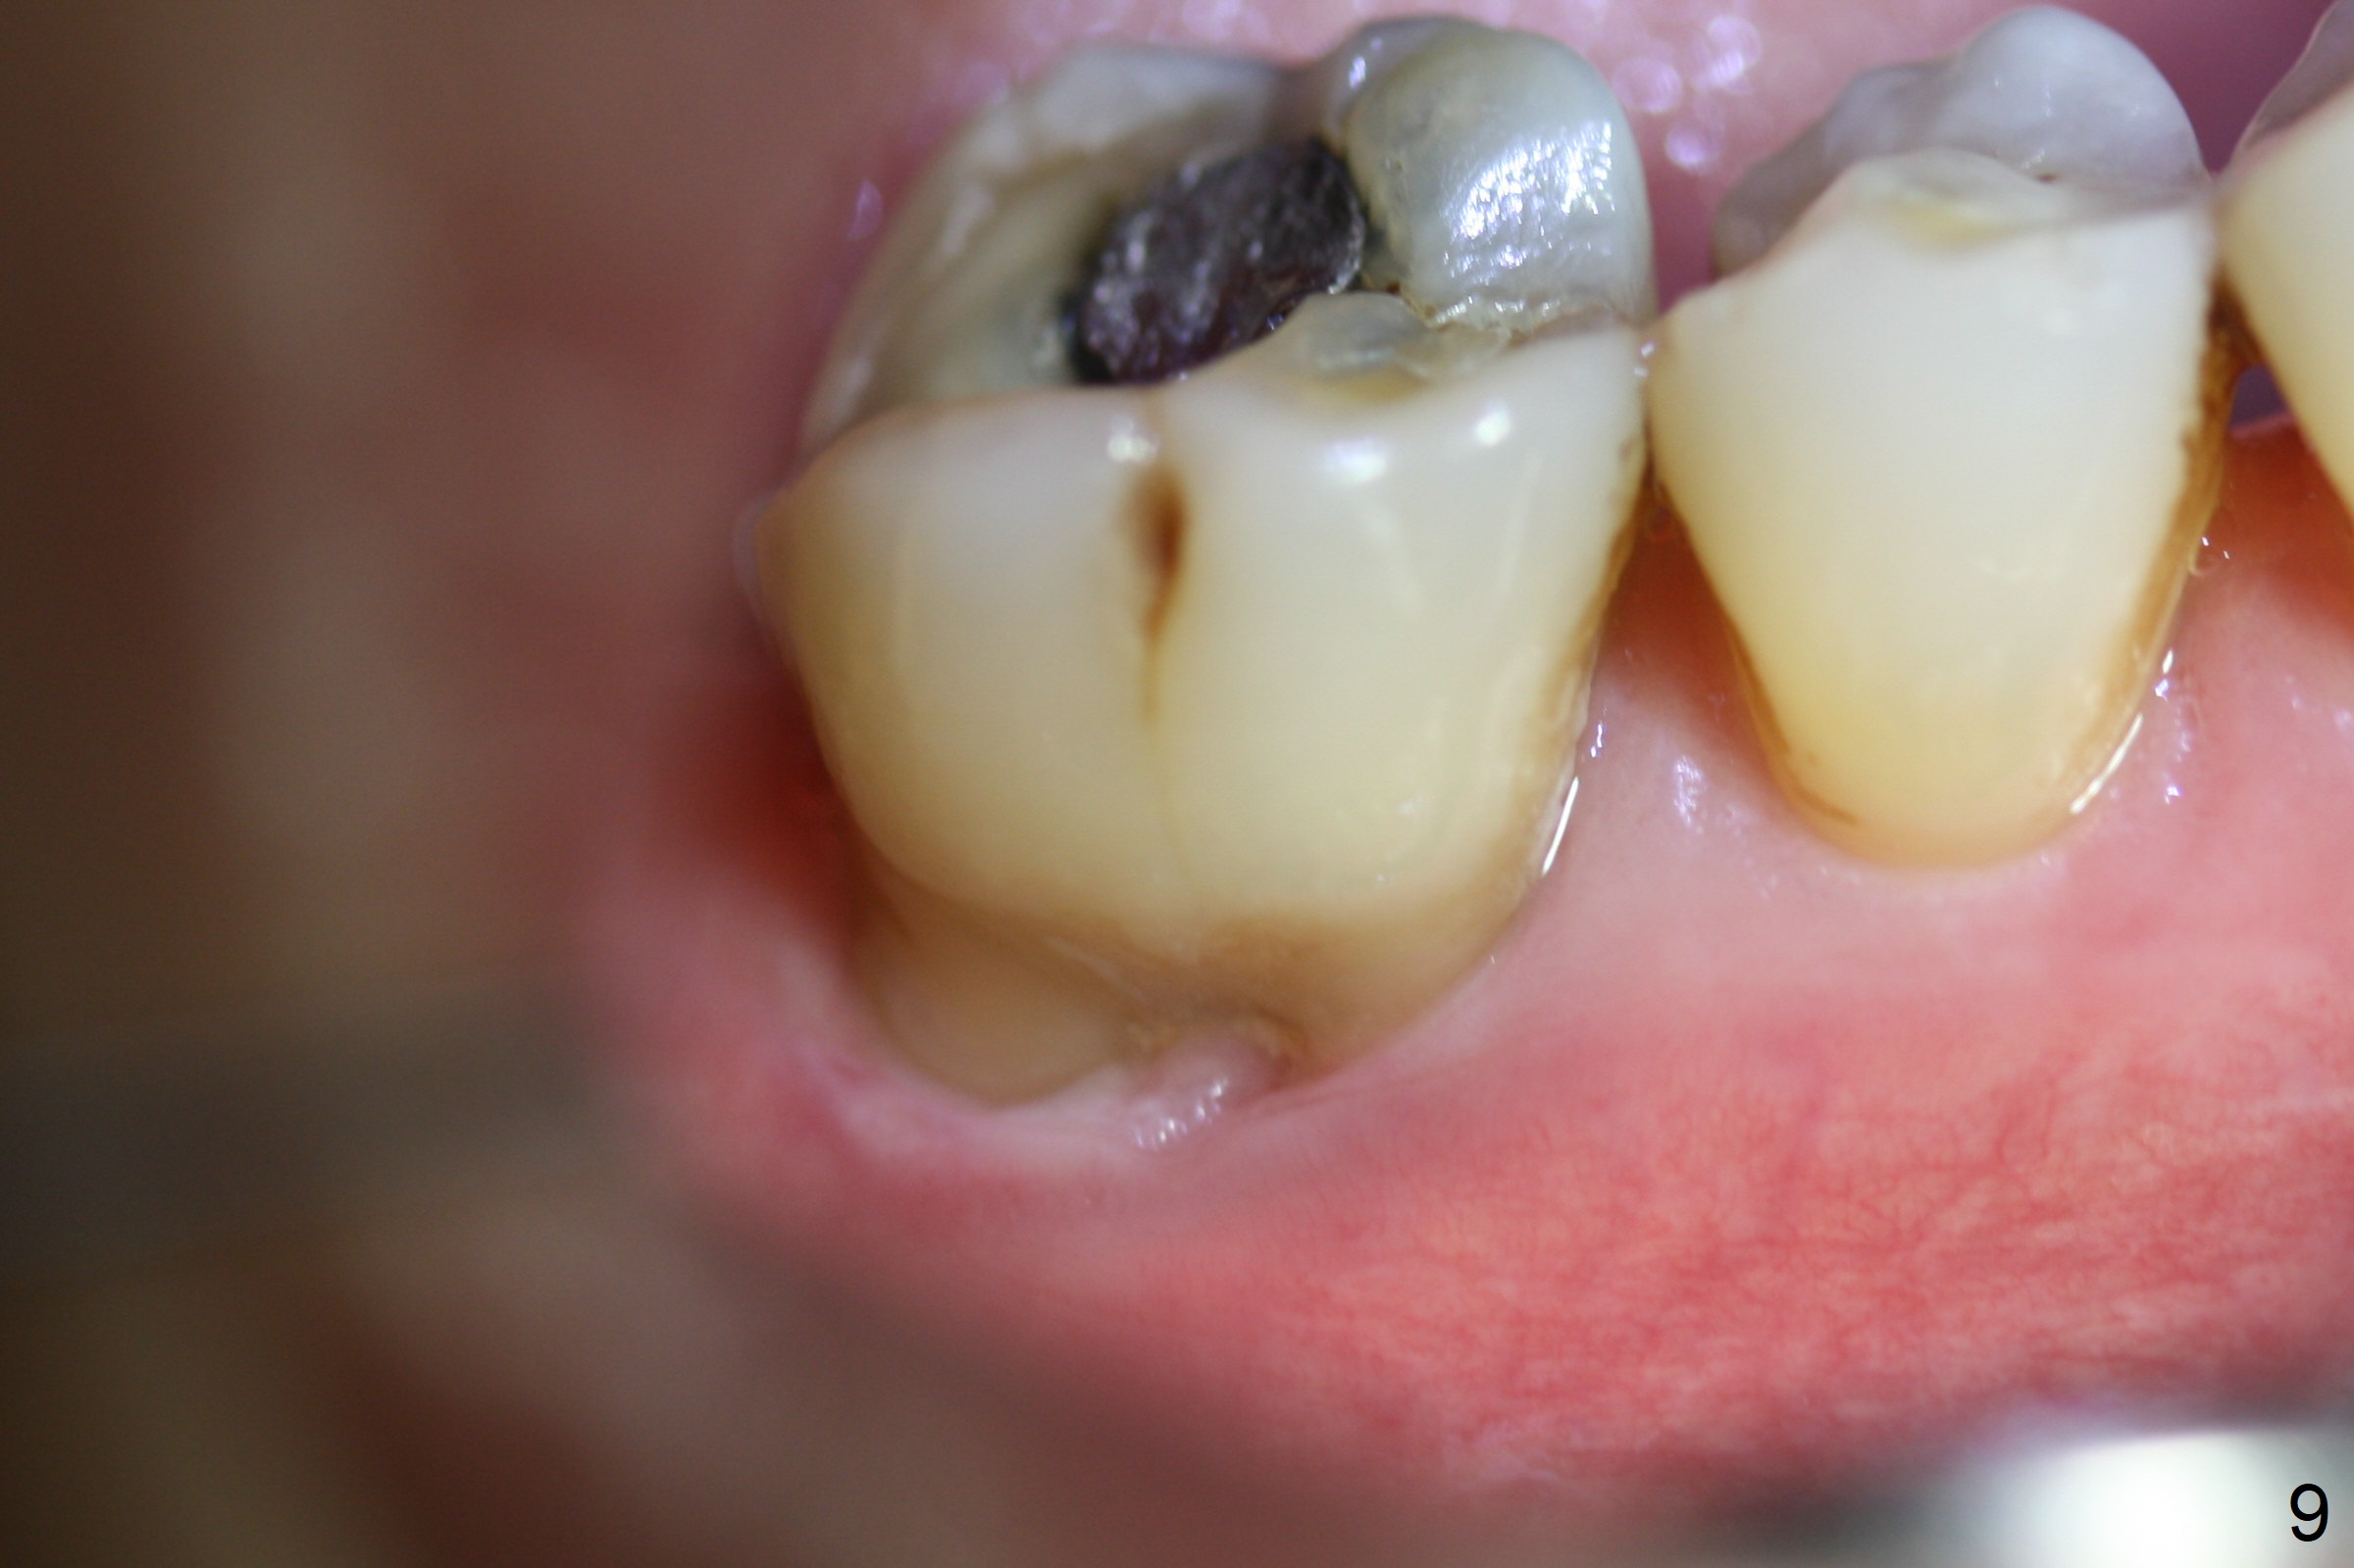

A 71-year-old woman (bruxer) wants to remove the tooth #30 (occlusal trauma, possible root fracture) for implant following the one at #14 (Fig.1). IBS abutment screw tends to loosen in functioning if the implant is placed too deep and/or off the longitudinal axis. If these two conditions are not controlled well, switch to a large tissue-level implant. A drawback of placing the implant in the septum is that the mesial margin of the abutment (Fig.2 pink) is subcrestal. If the implant is placed in the mesial socket (Fig.5 red line), the imagined abutment margin plane (white line) is parallel to the mesiodistal crests. Initial osteotomy entry point in the mesial socket and trajectory should be adjusted intraop (compare Fig.6 and 7) so that the apex of the implant will not be too close to the apex of the tooth #29 (to avoid truncating the neurovascular supply to the tooth (Fig.6 red arrowheads)) at the same time the abutment inclination is not too compromised (Fig.7). To prevent pressure upon the buccal (Fig.4 B) plate, osteotomy should be slightly lingual and/or the diameter of the implant is to be < 7 mm. Use a 3 mm unipost for provisional and probably 5 mm one for definitive restoration. Apply bonding to the post if the implant is 6 mm or less. The provisional margin should be wide and deep for deep margin and easy impression later. Use IS drills with 4 mm stopper for osteotomy if the septum is absent. Prepare Rongeur and surgical handpiece to remove the remaining septum if needed. Be wary of the distally curved root tip of #29. In fact there is a mesiodistal crack line (Fig.8 arrowheads) with buccal recession (Fig.9, 2 weeks preop).